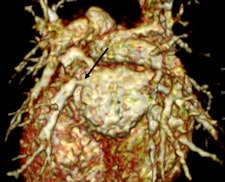

MDCT using a low radiation dose protocol is the best diagnostic tool for assessing the central airway, cardiovascular and mediastinal abnormalities, and the lung parenchyma in children, and the relevant information can be acquired with a single-volumetric data set acquisition, she stated. Using thin-slice collimation acquisition with inherent isotropic resolution, the image data can be manipulated and reformatted to display 2D and 3D images with the same spatial resolution as the axial images, thus enhancing diagnostic accuracy and providing data that can be used in presurgical planning and patient management.